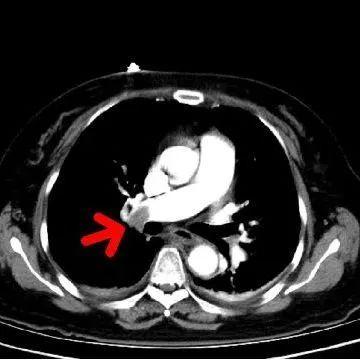

术中造影可见右肺动脉干充盈缺损,

轮廓僵硬,管腔狭窄

导管头顶入血栓中